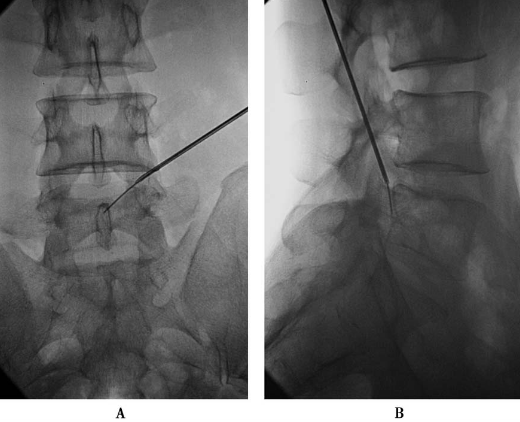

第三靶点:固定导丝,退出2级环锯、2级扩张管和2级导杆,导丝固定不动,沿导丝:

①置入3级导杆使头端到达第二靶点(图21);

图21 置入3级导杆,前后位透视:头端到达第二靶点

②拔出导丝,将导杆尾端压向腹侧,用锤子敲打导杆尾端,使导杆头端在L5椎体后缘潜行到达第三靶点(图22);

图22 拔出导丝,将导杆尾端压向腹侧用锤子敲打导杆尾端,使导杆头端在L5椎体后缘潜行到达第三靶点